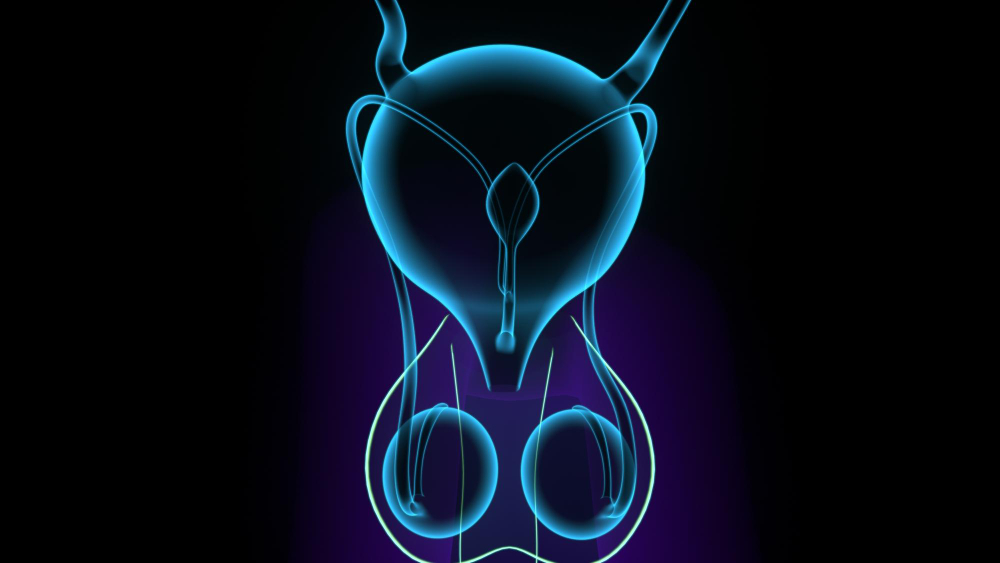

הערמונית, מזכירה בצורתה את הערמון מכאן שמה בעברית, ממוקמת מתחת לשלפוחית השתן וסובבת את השופכה, אשר עוברת דרכה. לכן, כאשר הערמונית גדלה – היא עלולה ללחוץ על השופכה ולגרום לקשיים בהתרוקנות, זרם שתן חלש, לצורך תכוף במתן שתן, להטלת שתן לילית, ומאידך אף לעצירת שתן מוחלטת או לזיהומים חוזרים. אמנם מדובר בבעיה שאינה מסכנת חיים, אך היא עשויה להשפיע רבות על התפקוד היומיומי, על איכות השינה, ועל איכות החיים האישית של המטופל.

בלוטת הערמונית ממוקמת כאמור מתחת לשלפוחית השתן והשופכה עוברת דרך בלוטה זו. במהלך החיים, במיוחד מגיל 50 ואילך, הערמונית נוטה לגדול. מדובר בתהליך טבעי הקשור לשינויים הורמונליים – בעיקר ברמות הטסטוסטרון והדיהידרוטסטוסטרון (DHT). ההגדלה גורמת ללחץ על השופכה ולפגיעה בזרימת השתן. מדובר בבעיה שאינה ממארת, אך בעלת השפעה ניכרת על איכות החיים. נתונים עדכניים מצביעים על כך שכ־50% מהגברים בגיל 60 סובלים מהגדלה שפירה של הערמונית, ובגיל 80 – למעלה מ־80% מהגברים מושפעים ממנה.

TURP – כריתה של הערמונית דרך השופכה

השיטה הוותיקה והנפוצה ביותר. מתבצעת דרך השופכה ללא חתכים חיצוניים. במהלכה מוסרת רקמת הערמונית החוסמת באמצעות לולאה חשמלית. מתאימה בעיקר לערמונית בגודל קטן עד בינוני.

ניתוח בלייזר (HoLEP)

שיטה מתקדמת בה מוסרת הרקמה החוסמת בעזרת קרן לייזר. הלייזר מאפשר דיוק גבוה, הפחתת דימום וחזרה מהירה יותר לשגרה. מתאים במיוחד לחולים הנוטלים נוגדי קרישה ולבעלי ערמונית גדולה.